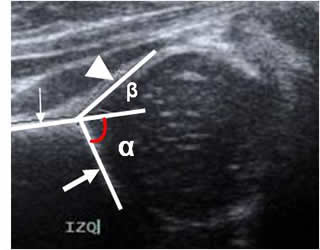

Angulo alfa:

Trazo sobre una vista coronal de ecografía, sobre la parte media del acetábulo. Se mide entre la línea de base (Prolongación del iliaco) y la línea del techo óseo (Del borde inferior del iliaco, hasta el extremo óseo del acetábulo). Representa la excavación ósea del acetábulo y su amplitud normal debe ser igual o mayor de 60º y disminuye en casos de displasia. (19, 20). (Fig 62).

Un ángulo mayor de 60º es normal para cualquier edad. Entre 50º y 59º, puede ser normal para niños menores de 3 meses, pero se recomienda el seguimiento y un ángulo menor de 50º, es anormal en cualquier edad. (19). (Fig 64).

Fig 62. Angulos de la cadera.

Ecografía. Línea de base (Flecha delgada), línea del techo óseo (Flecha gruesa) y línea del techo cartilaginoso (Punta de flecha). Angulo alfa normal, con amplitud mayor de 60.